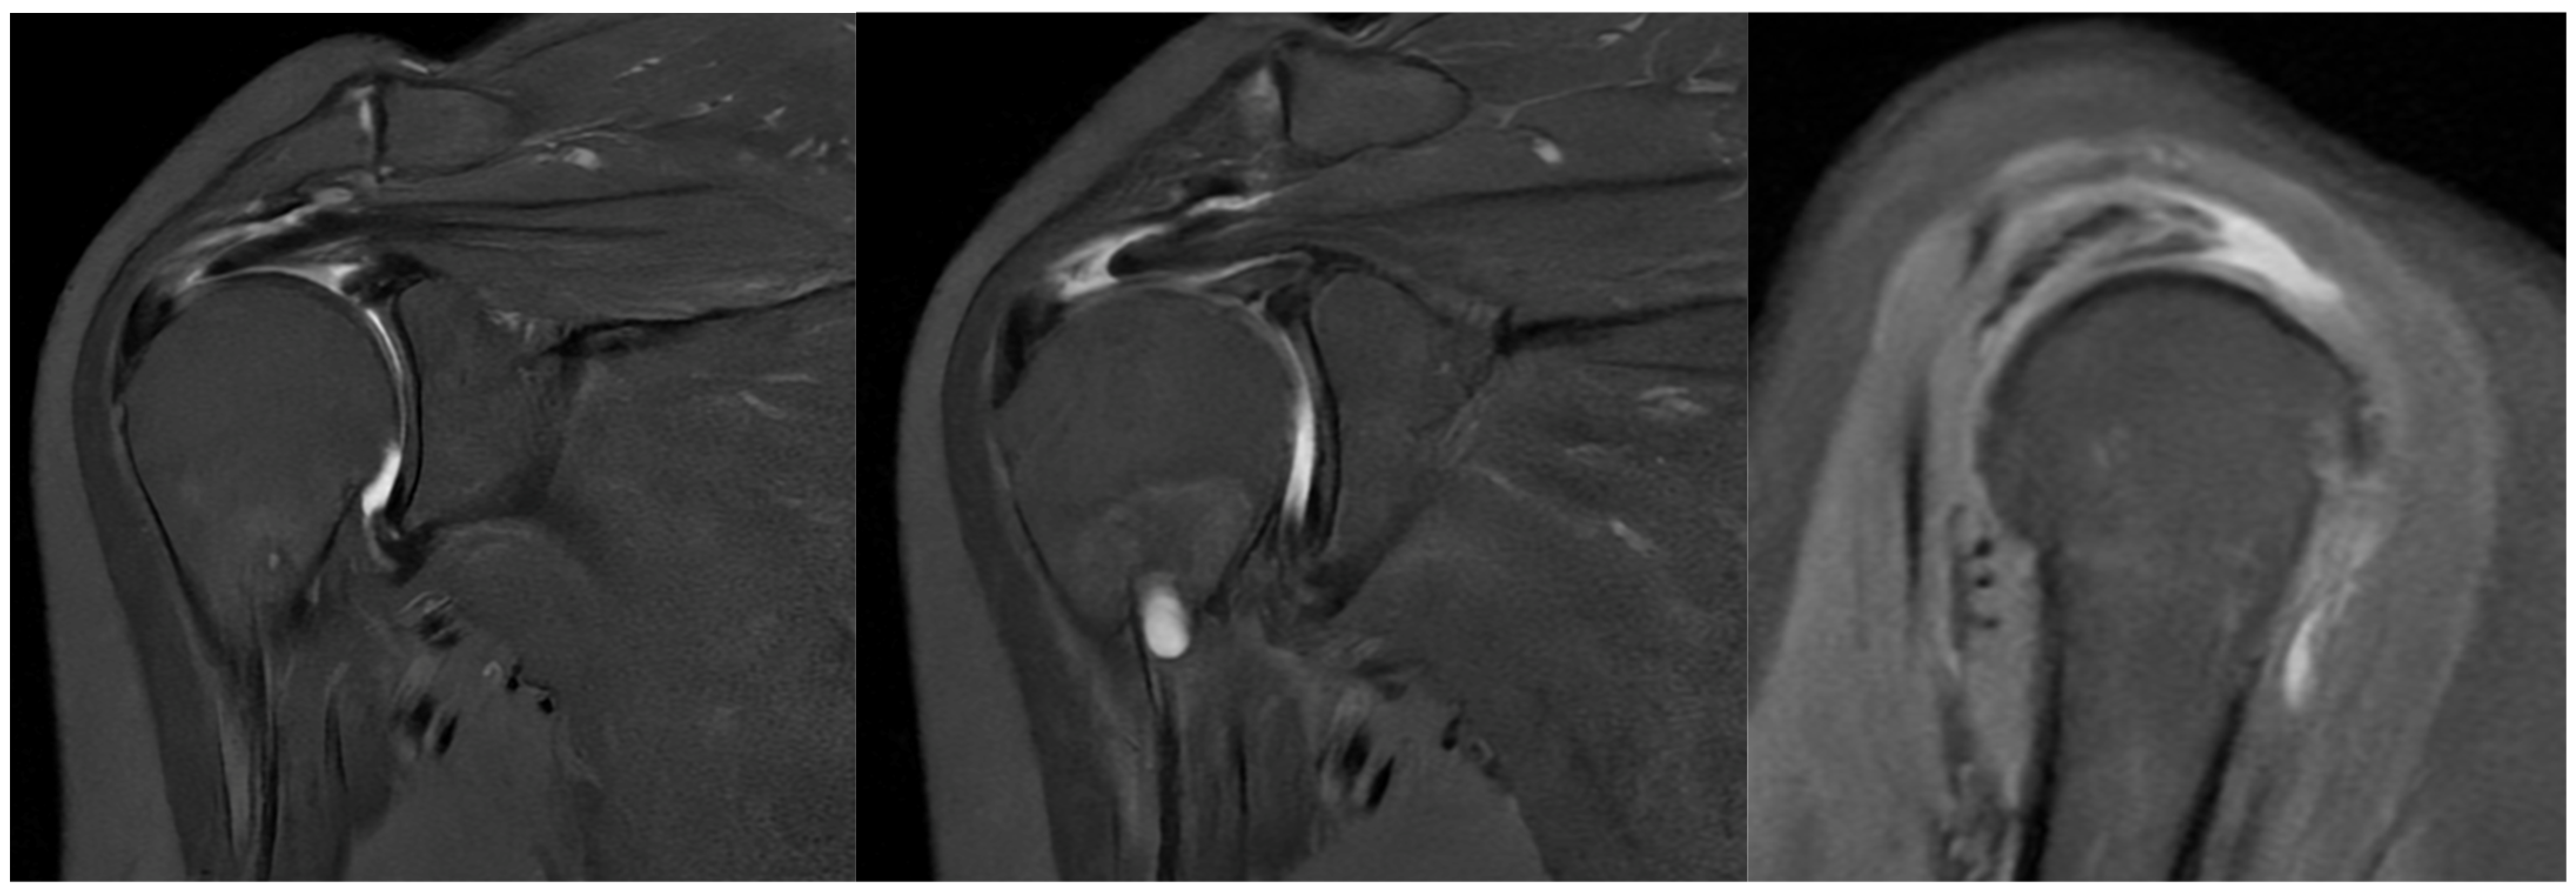

On physical examination, clinical findings included positive impingement signs, weakness in shoulder abduction and external rotation, restricted range of motion, and tenderness to palpation over the lateral aspect of the right shoulder, corresponding to the anatomical location of the rotator cuff tendons. Magnetic resonance imaging (MRI) corroborated these findings, revealing a full-thickness tear involving the supraspinatus and infraspinatus tendons (Figure 1).

Figure 1.

Preoperative MRI showing full-thickness rotator cuff tear.

Taking a closer look at preoperative MR images, it is possible to glimpse the line of the tear, which is oblique, and the two sheets of the tendon, which have different degrees of retraction (Figure 12).

Figure 12.

Preoperative MRI with identification of the line of the tear and the two separated sheets of the supraspinatus tendon, with different retraction.

Preoperative magnetic resonance imaging can reveal the orientation of the tear, and the varying degrees of retraction in the tendon sheets. However, while imaging provides insight into tendon retraction, it does not yield information about the elasticity of the tissue, which can only be accurately assessed during an arthroscopic examination. Arthroscopy in the presented case revealed the separation of sheets 2 and 3 within both the infraspinatus and supraspinatus tendons. Both sheets of the infraspinatus tendon were deemed repairable, while sheet 2 of the supraspinatus tendon could not be adequately repositioned. Consequently, following the rotator cuff repair, a defect remained in the supraspinatus tendon, which the senior Author opted to address with the application of a Regeneten implant.